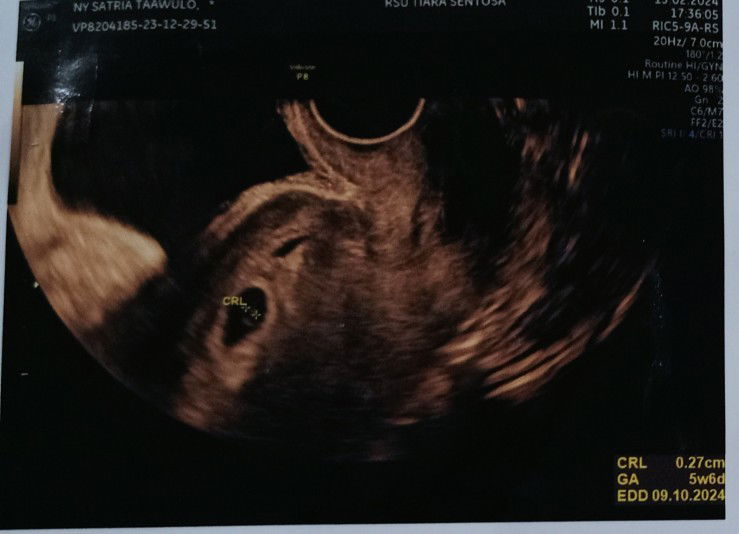

Halo bunda...mungkin ada yg samaan, dikehamilan memasuki 6 W yg tadinya gak ngerasain apa apa kini mulai muncul keluhan... terutama di malam hari, kepala pening, mata pekat tp GK bisa tidur, lbih terasa mualnya pas masuk magrib...belum perna ke dokter, nanti masuk 7 W baru rencana U SG #, tp sudah rutin minum vitamin n susu hamil